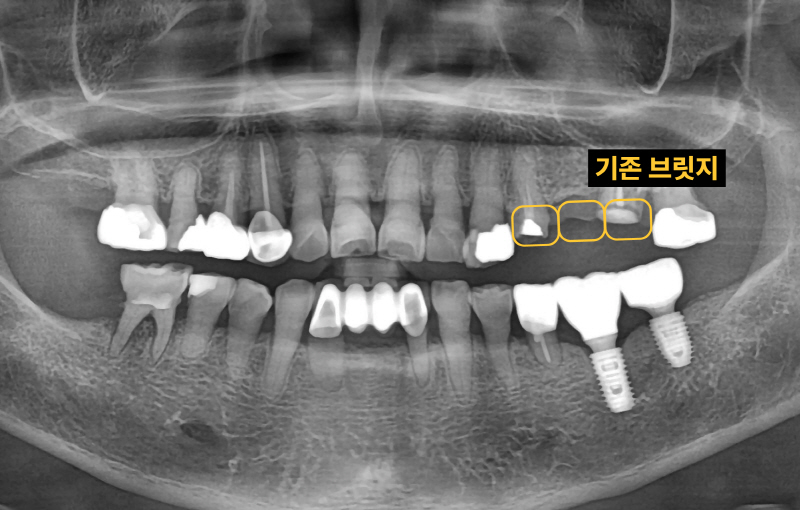

"기존 브릿지가 흔들리고 깨졌어요" 60대 여자 환자분이었습니다. 기존 브릿지를 다시 살릴 수 있는지 확인합니다.

이미 신경치료된 치아 뿌리 끝에 염증이 잡혀있고 브릿지 아래로 2차충치가 크게 생겨서 임플란트로 치료 계획을 정했습니다. 임플란트 2개를 심고 치아 머리(크라운) 3개를 만듭니다. 여러 개의 임플란트를 심을 때 꼭 개수대로 임플란트를 심을 필요는 없습니다. 과거에는 발치, 상악동 수술, 임플란트를 전부 기다리며 나눠서 진행했는데 시간이 너무 오래 걸립니다. 저는 최대한 치아가 없는 기간을 단축시키기 위해서 치아를 뽑고(발치) 동시에 임플란트를 심으며 뼈가 없는 경우 상악동 수술을 동시에 진행합니다.

발치, 상악동 거상, 임플란트 식립 모두 이상적인 모습입니다. 과거 임플란트가 없던 시절에는 브릿지 치료가 일반적이었습니다. 하지만 현재는 치아가 없을 때 양 옆의 치아를 갈아서 씌우는 치료는 임플란트 등장으로 없어지고 있습니다. 또한 오래된 브릿지가 흔들리거나 잇몸에 염증이 생긴다면 임플란트로 교체가 필요할 수 있습니다.